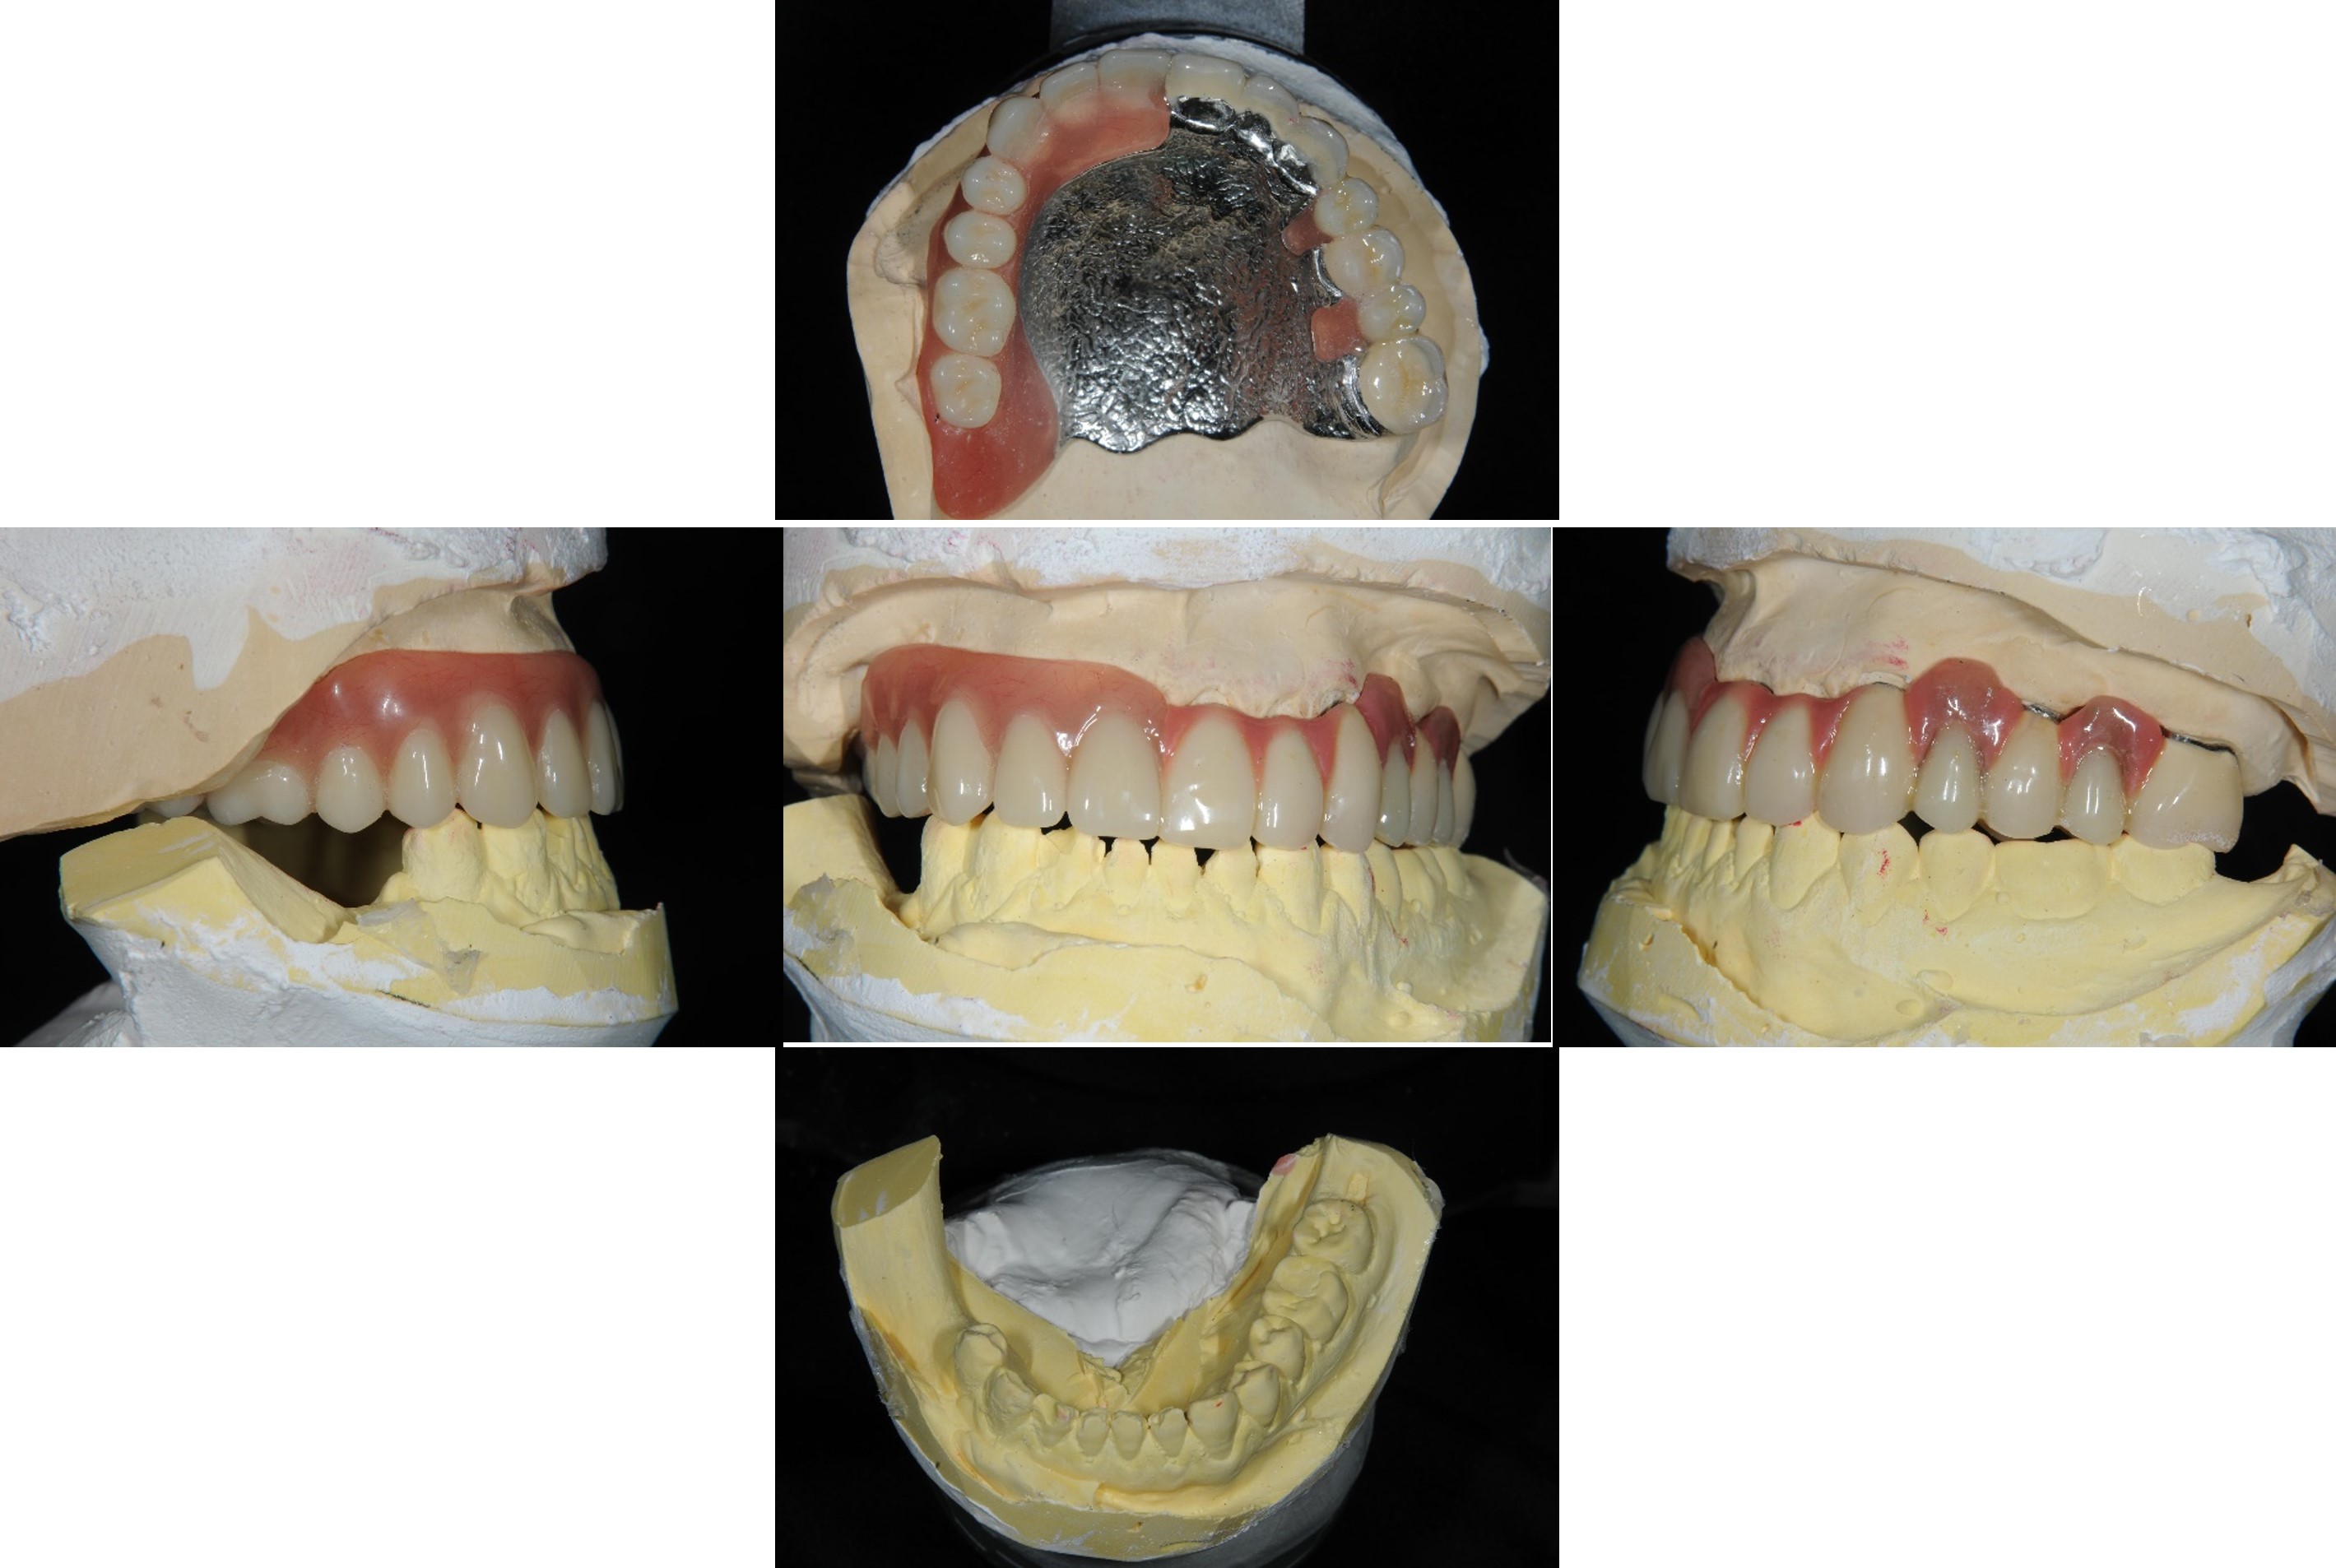

內外冠及活動假牙

內外冠支撐活動假牙

覆蓋型活動假牙

透過定位器與內外冠的輔助,活動假牙更穩定,咬合功能更理想。